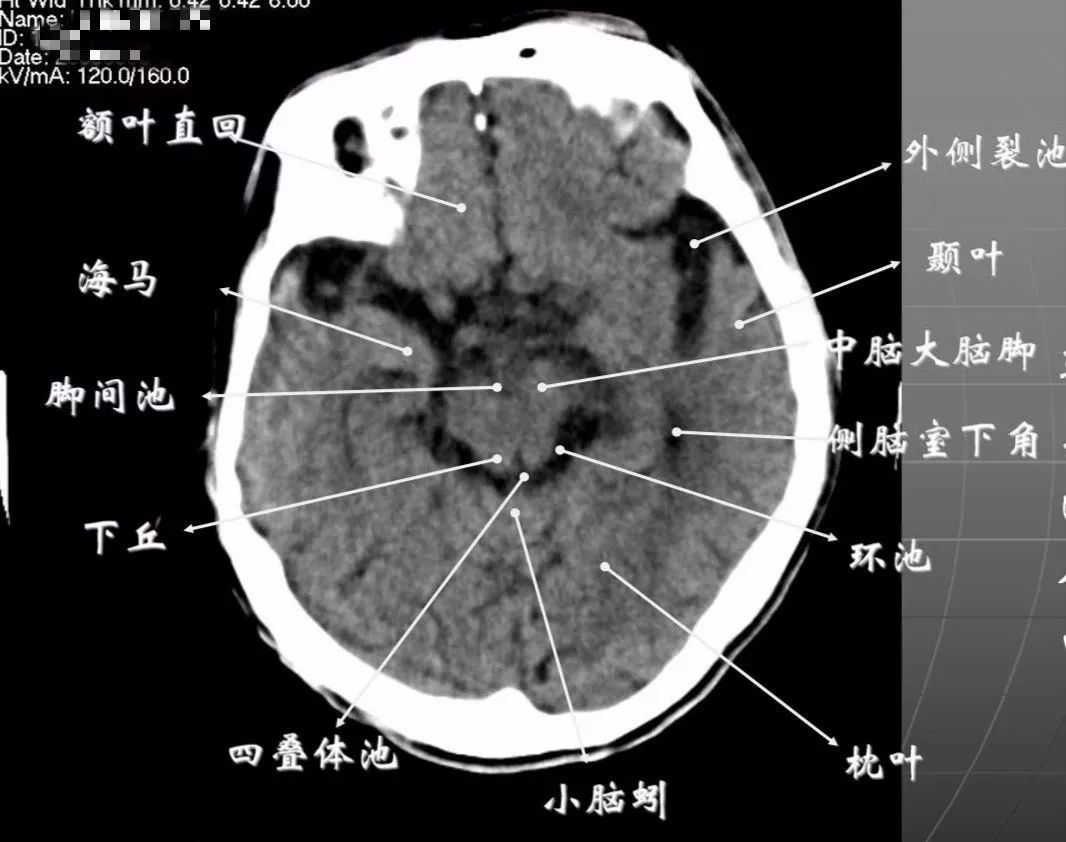

2、鞍上池层面颅前窝:颞叶。

鞍上池:在垂体窝上方,位于两侧颅中窝之间,前界为颞叶直回,侧方位颞叶海马,呈五角星形或六角星形。其前角连于纵裂池,两外侧角连于外侧裂池,两后外侧角延续于环池,第六个角位于后缘中间,是角间池。鞍上池边缘为大脑动脉环,池内前部常可见“V”字形视交叉。

颅后窝:四脑室或四叠体池。

3、第三脑室下部层面显示侧脑室前角的下部:

前方——额叶;外侧——尾状核头部;后方中线处——第三脑室,其两侧连接丘脑。

颅后窝:

“Y”字形或“V”字形的小脑幕,幕下结构在内侧(小脑上蚓部),幕上结构在外侧(枕叶)。

四叠体池:

位于小脑蚓部前方。